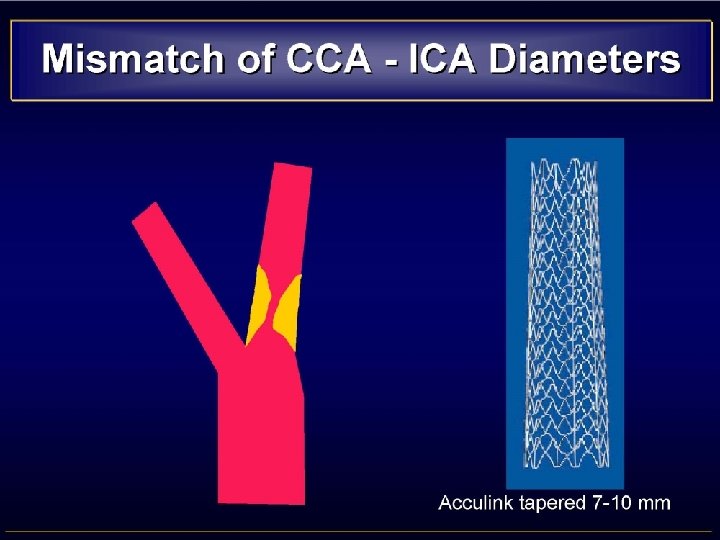

• MISMATCH CCA-ICA